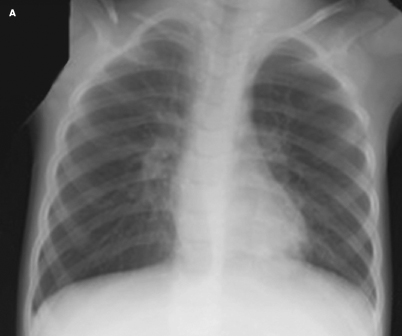

<div class="column"> <p>Case 1:</p> <p>For several weeks, this 72-year-old man has had progressive periorbital edema (A) that was initially thought to be allergic in...